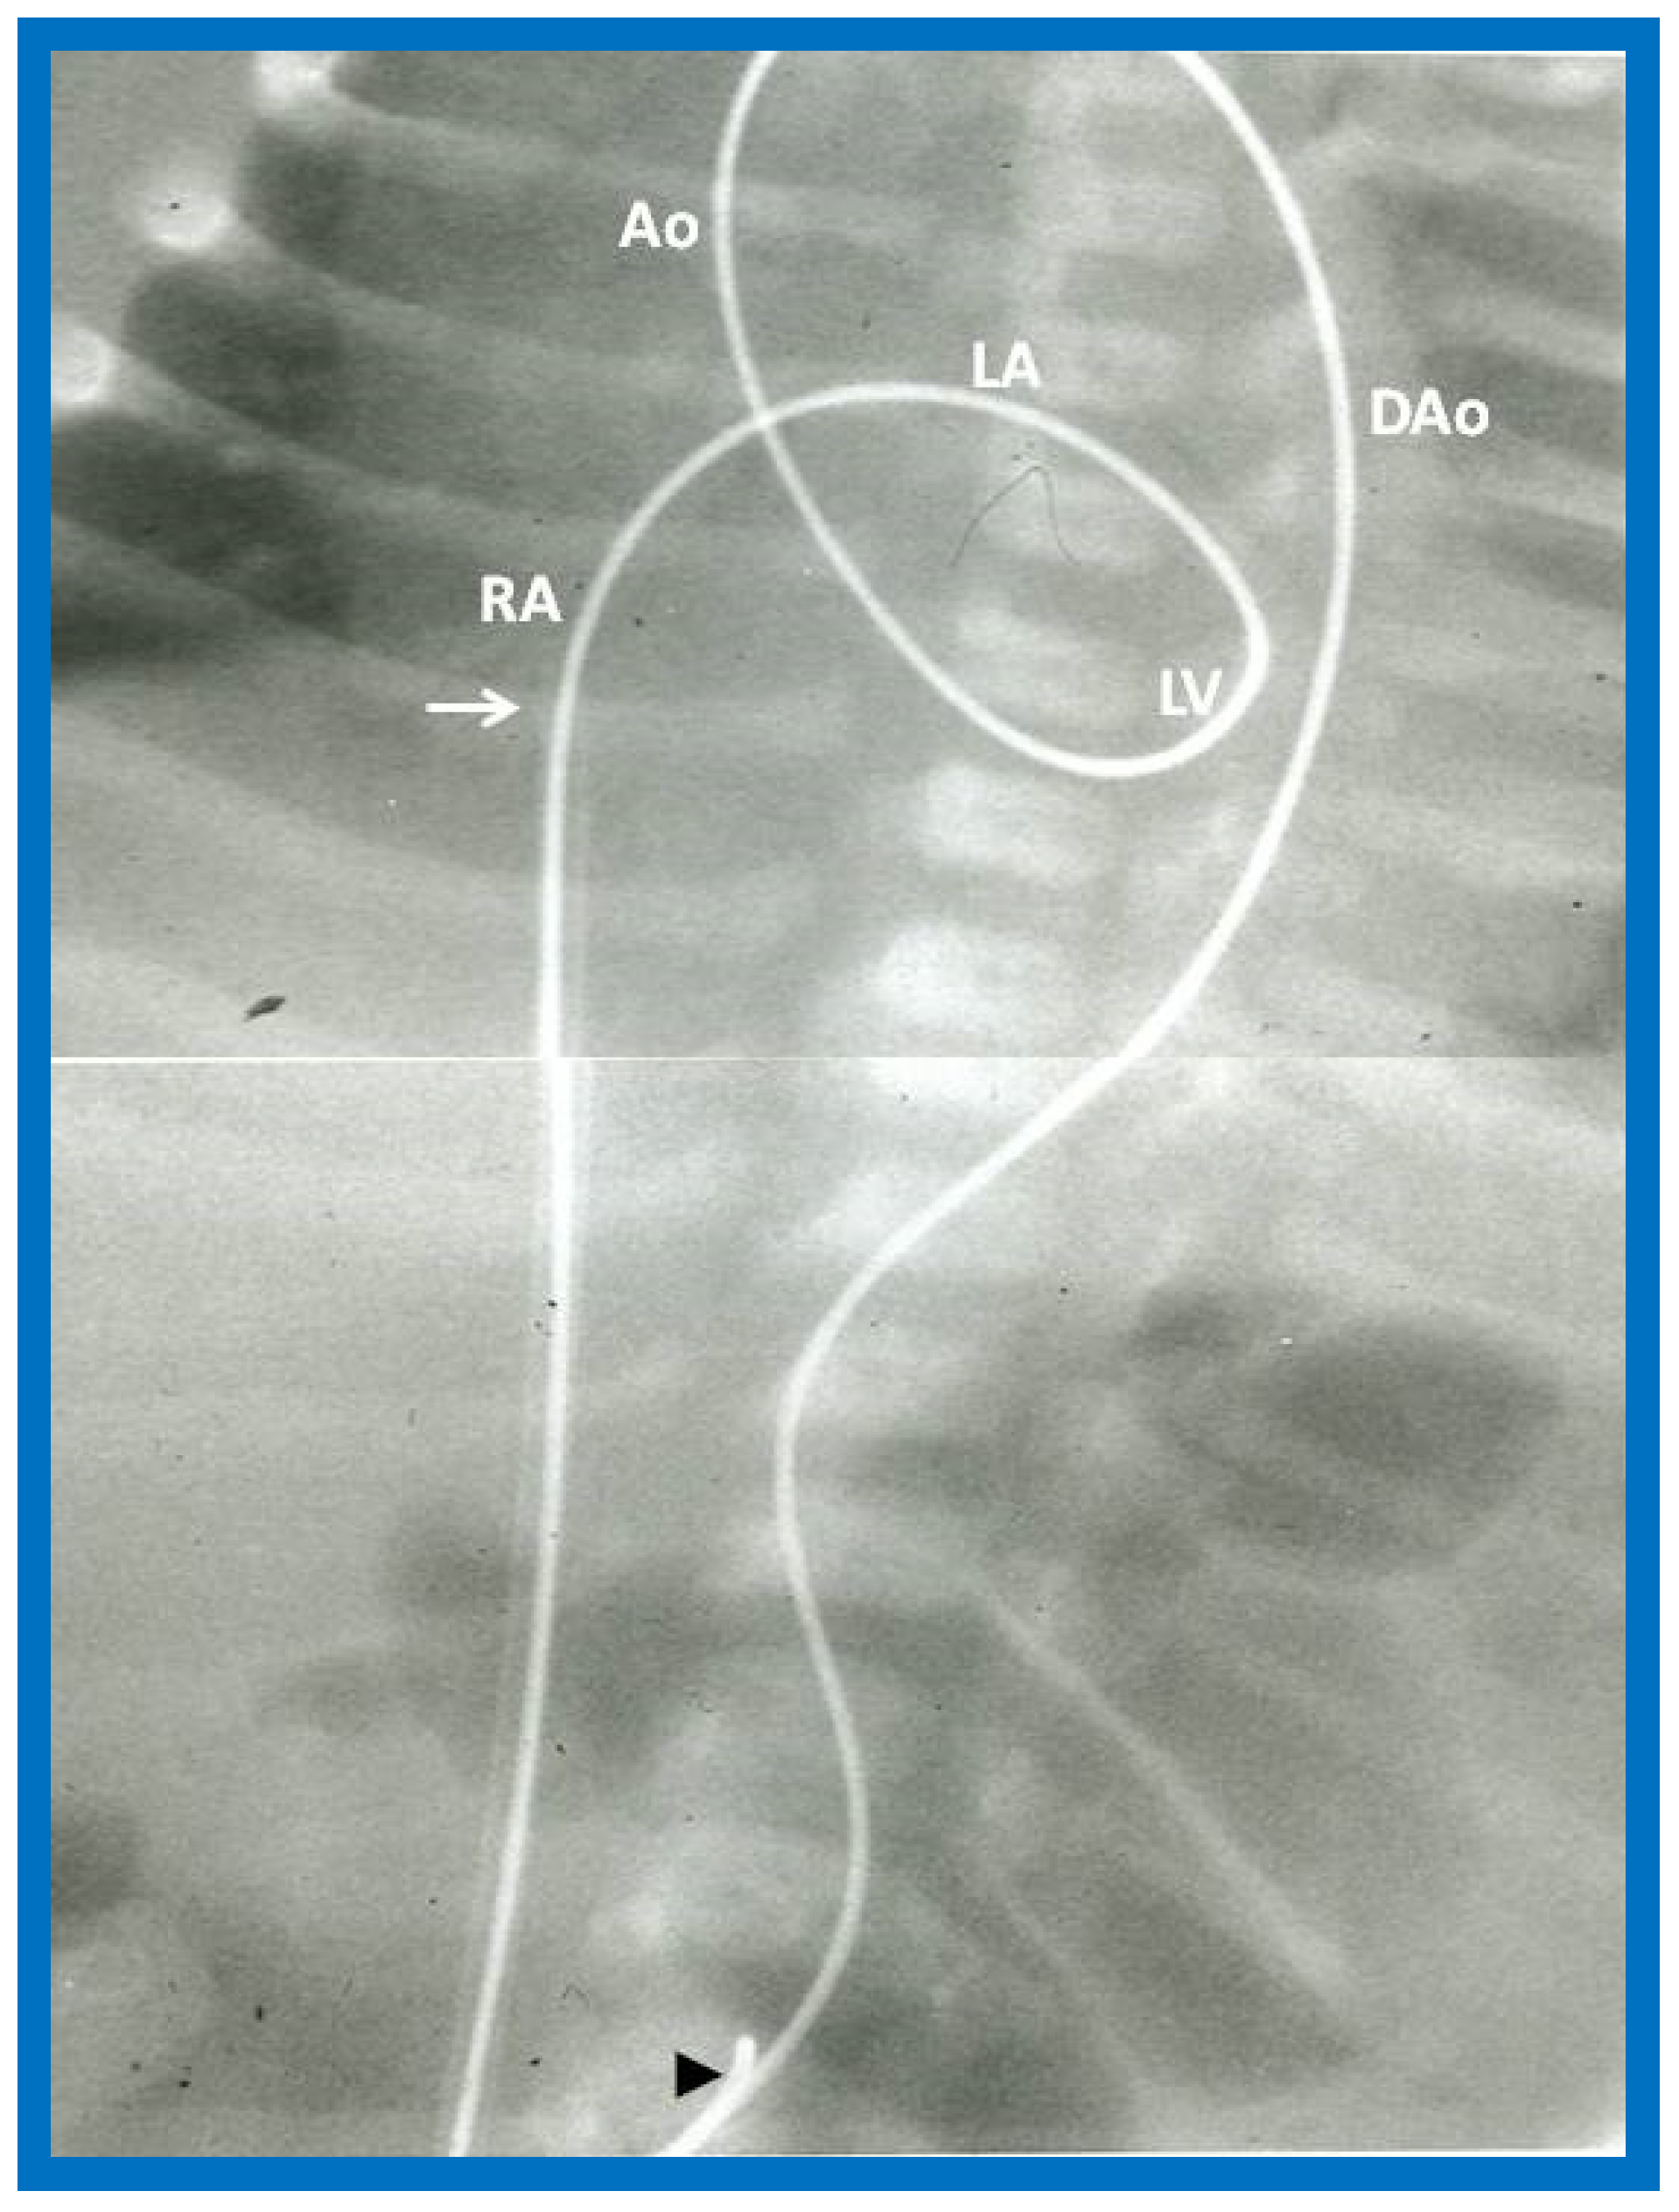

- Rao, P.S.; Jureidini, S.B. Transumbilical venous anterograde, snare-assisted balloon aortic valvuloplasty in a neonate with critical aortic stenosis. Catheter. Cardiovasc. Diagn. 1998, 45, 144–148. [Google Scholar] [CrossRef]

- Rao, P.S. Anterograde balloon aortic valvuloplasty in the neonate via the umbilical vein. Card. Cardiovasc. Interv. 2003, 59, 291–292. [Google Scholar] [CrossRef] [PubMed]

- Rao, P.S. Role of interventional cardiology in neonates: Part II-Balloon angioplasty/valvuloplasty. Neonatol. Today 2007, 2, 1–12. [Google Scholar]